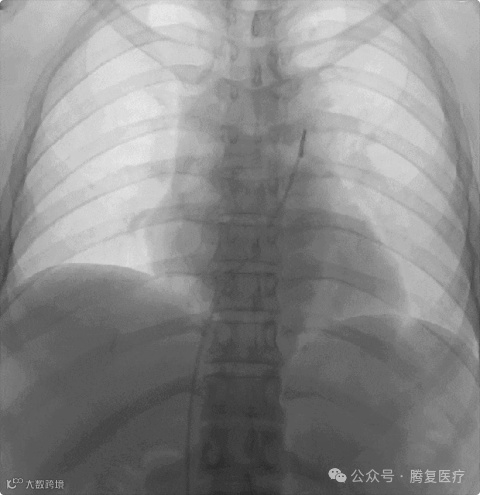

手术结束,复查造影提⽰左右肺动脉闭塞段复通,血栓负荷明显减少,继续予以后续抗凝治疗。

术后肺动脉复通